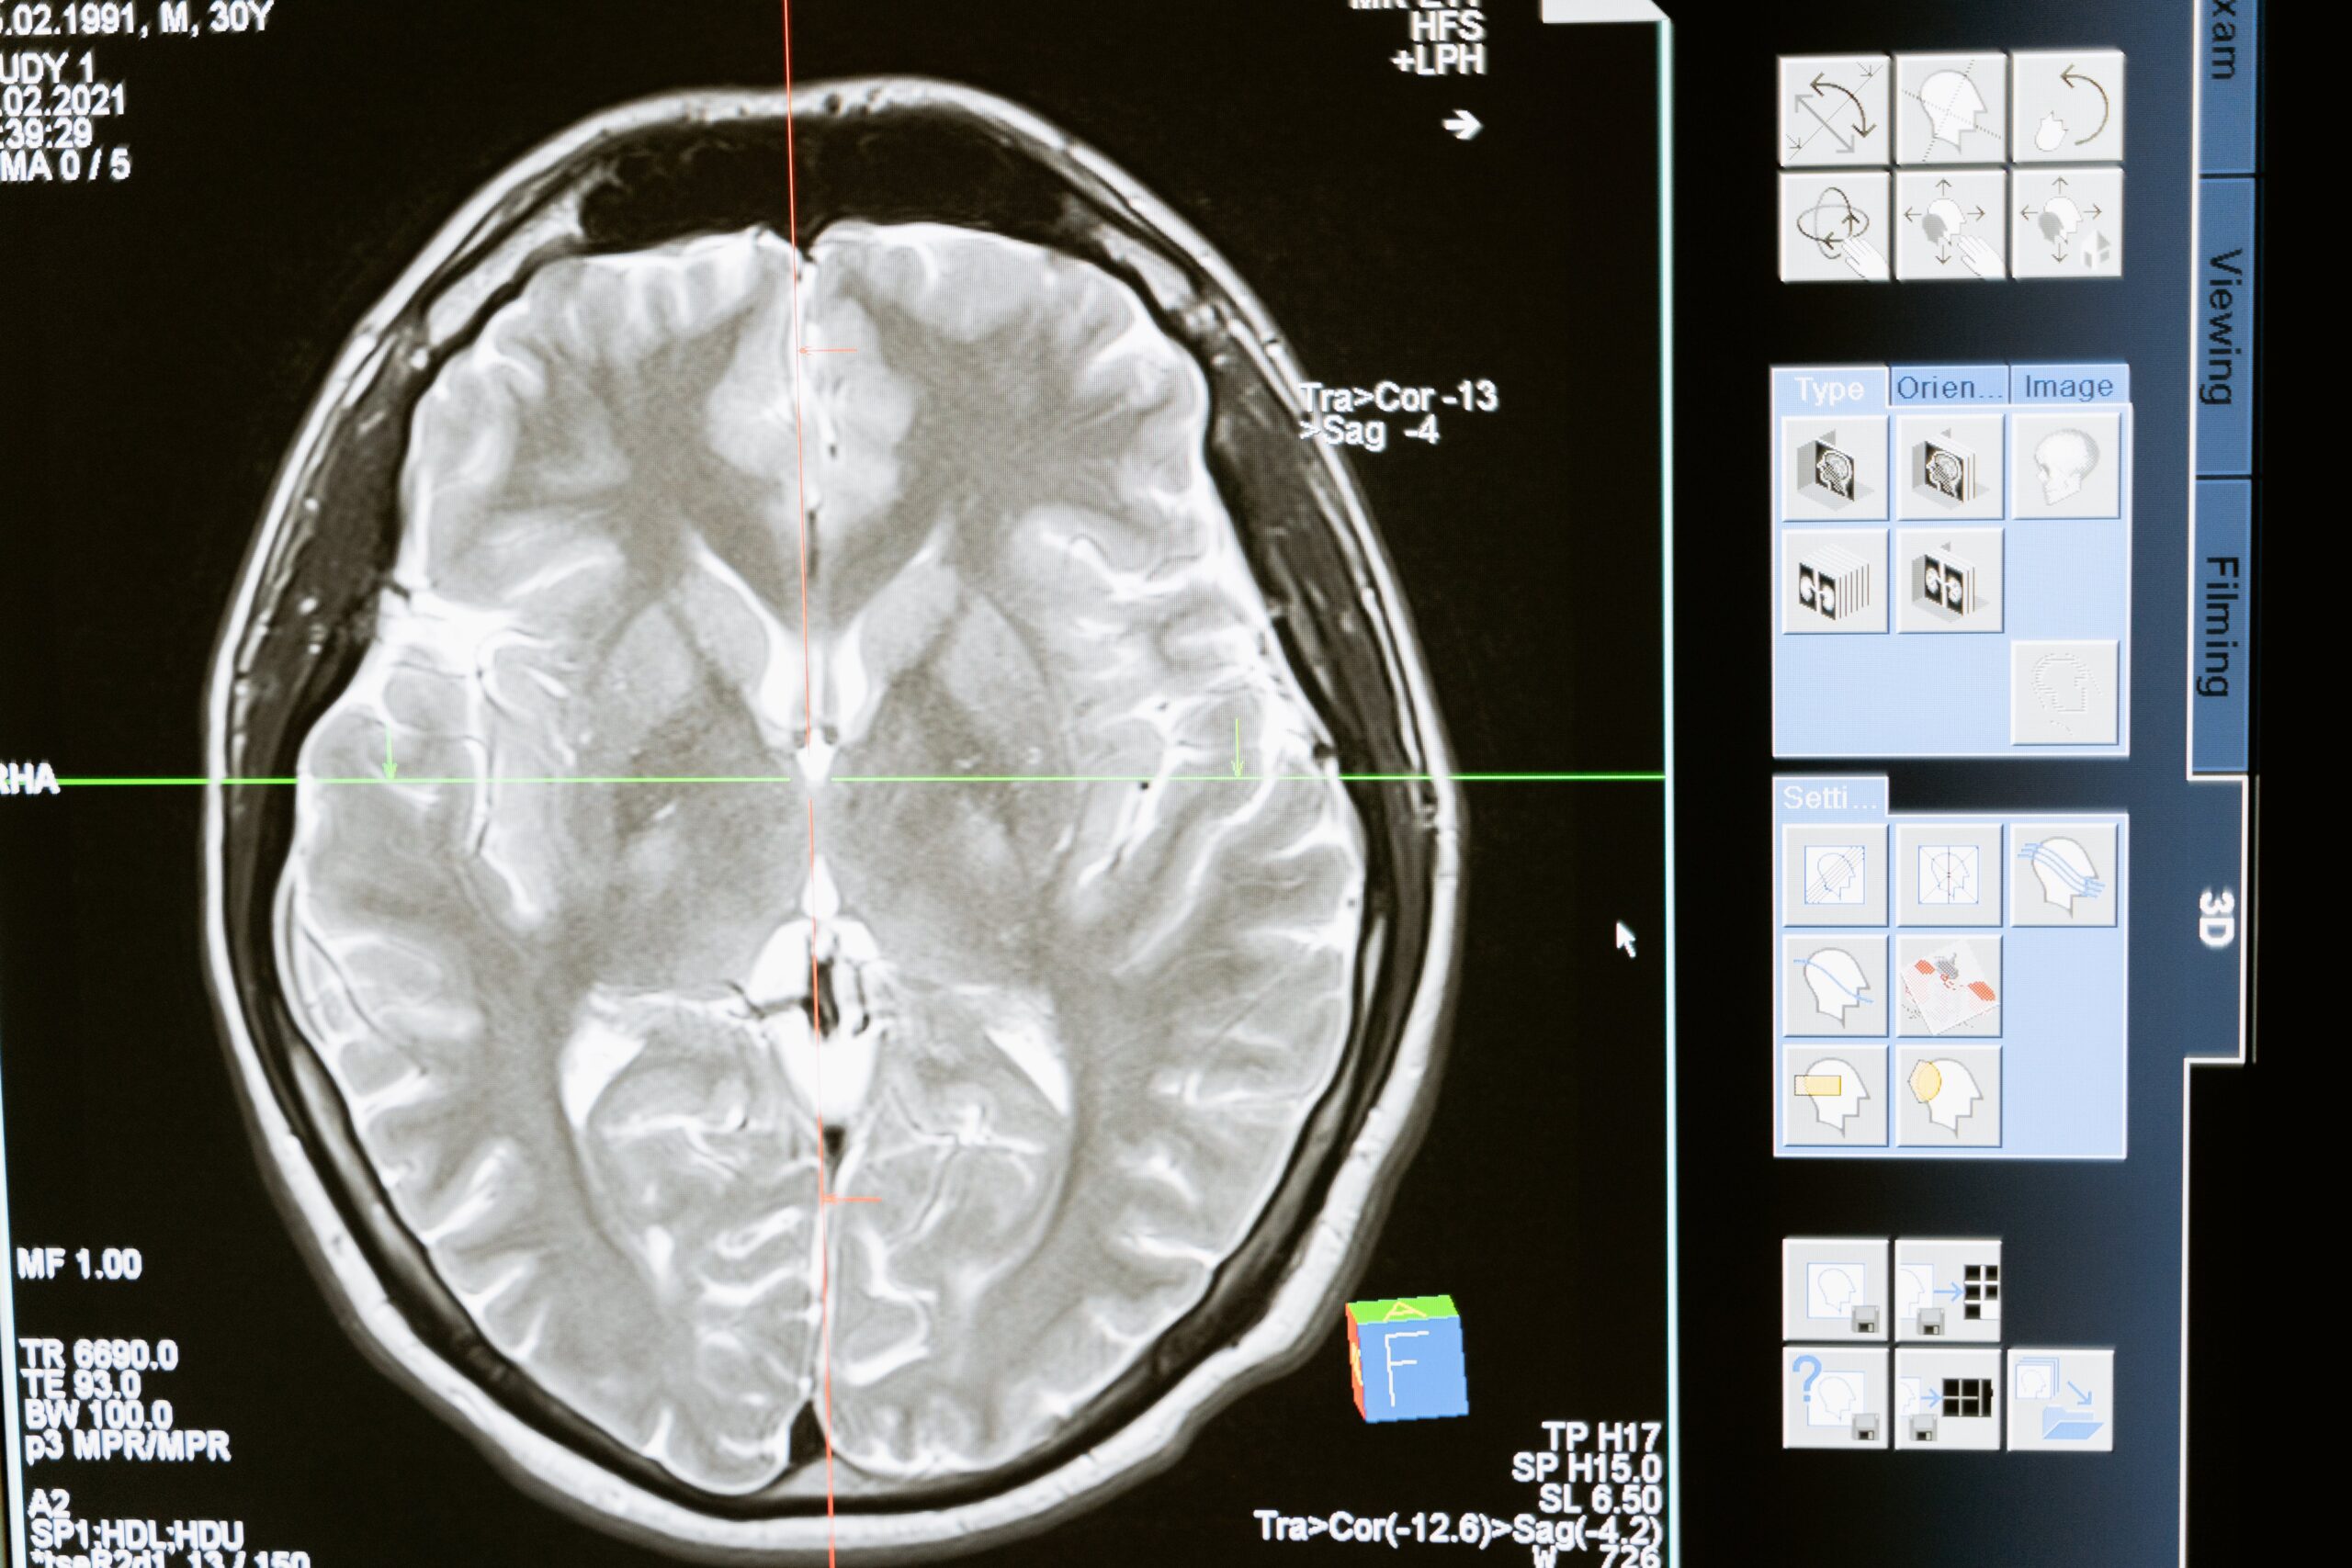

Image Analysis

An MIT-led team created a machine-learning method that can analyze 3D images up to a thousand times faster than what is now achievable because picture analysis takes a lot of time for human providers. This evaluation, which is done almost instantly, can give operating surgeons vital information. Additionally, it is envisaged that AI will aid in the development of upcoming radiology instruments that do not require tissue samples. Furthermore, AI image analysis could help rural locations without easy access to medical professionals and even improve telemedicine by enabling patients to take pictures of their bruises, rashes, or cuts with their phones and send them in to assess what care is required.